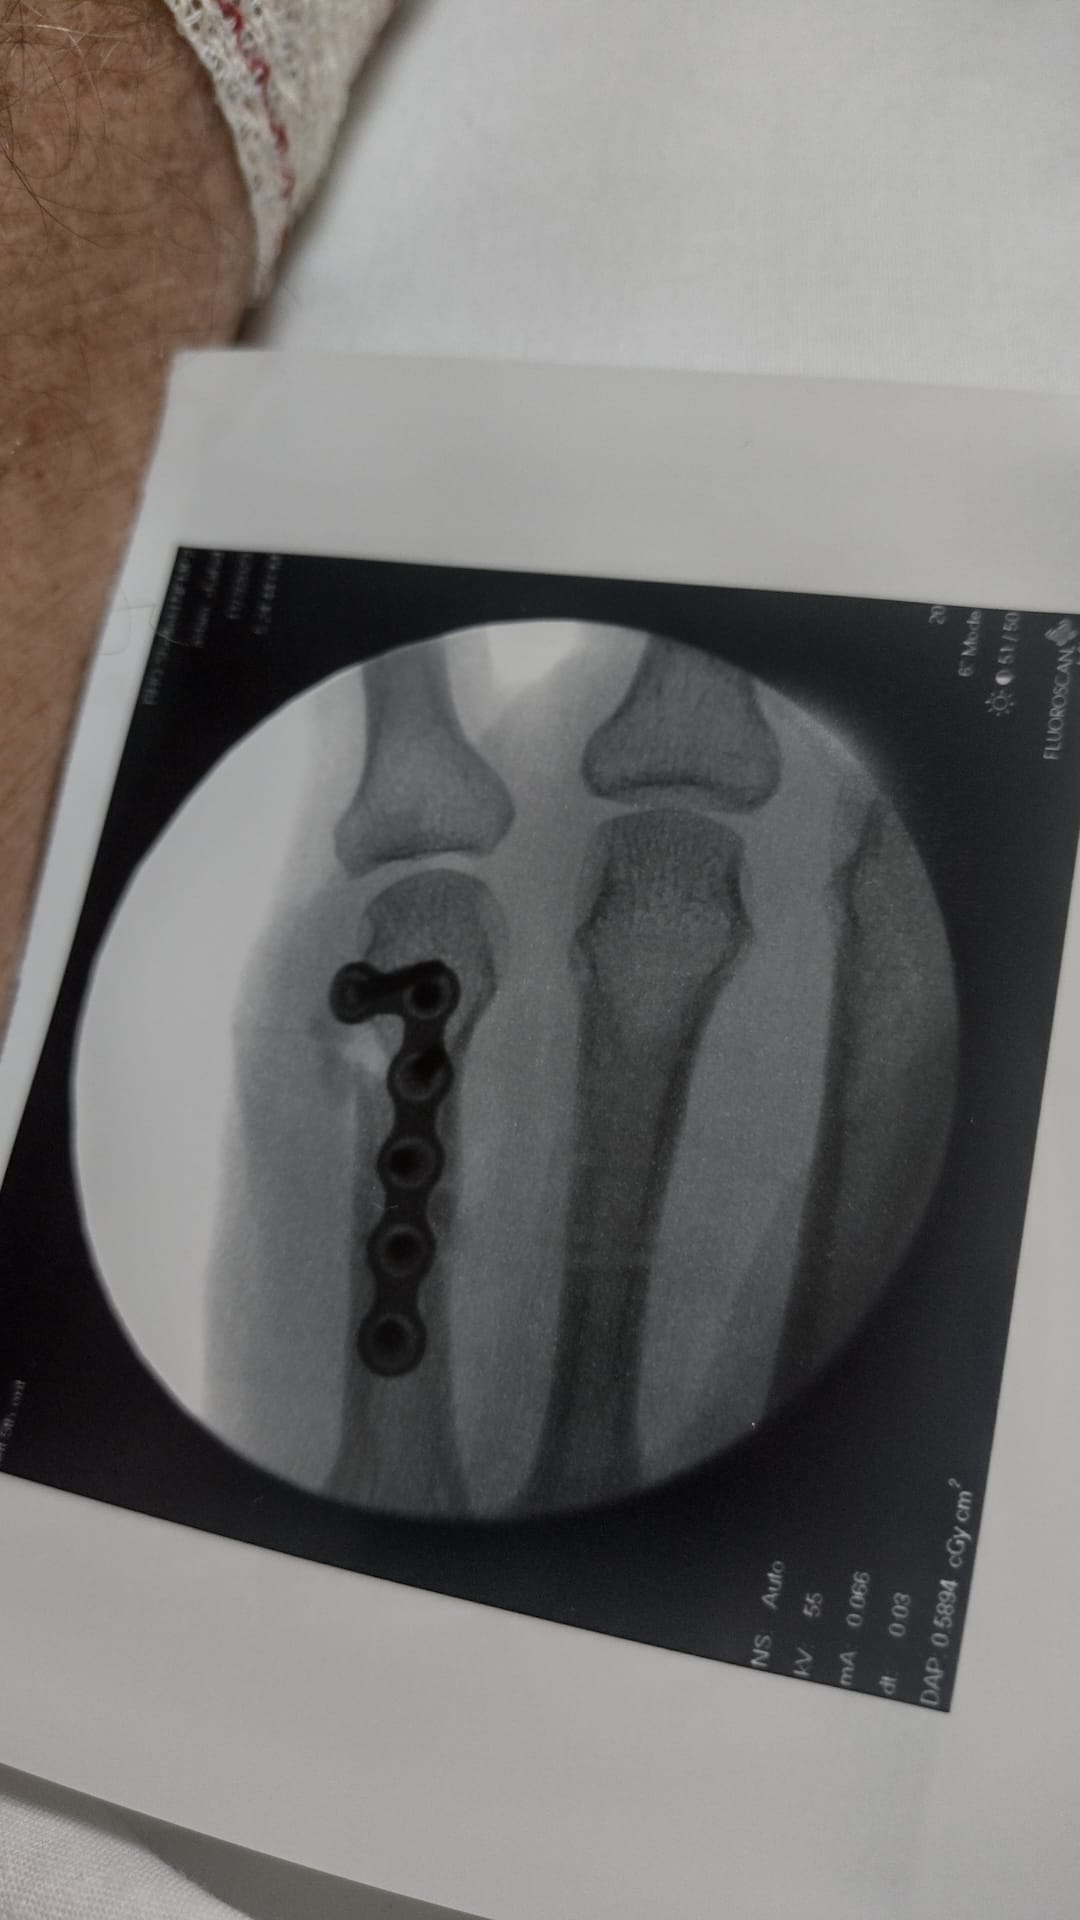

Last September, three days before the end of my Spanish holiday adventure, I decided to take a pootle into Salamanca along one of the many ‘greenways’ they have around Spanish cities. Near the end there was a little section of boardwalk off the side of a viewing platform of the Roman bridge so off I went. Literally… The front wheel slipped on the greasy surface and I landed on my left hand on the edge of the boardwalk. It hurt but I could still move my fingers so I set off back to the campsite. No sympathy from my partner but as my hand began to swell she did suggest I went to the hospital. However, we had a ferry to catch the following day so I thought it best to focus on getting back as the pain was bearable. Driving and taking bikes off and on of the bike rack was a bit uncomfortable though. Finally back in Sheffield, I trotted off to the minor injuries unit for an X-ray. The radiologist said “You’ve done a proper job on that!” and packed me off to the hand clinic. Two surgeries later and what looks on an X-ray like a piece of bike chain in the hand, the road (no mountain biking for a good while) to recovery started. Still a bit of discomfort eight months later but at least I am riding bikes off-road! Lesson: avoid family/commuter greenways.